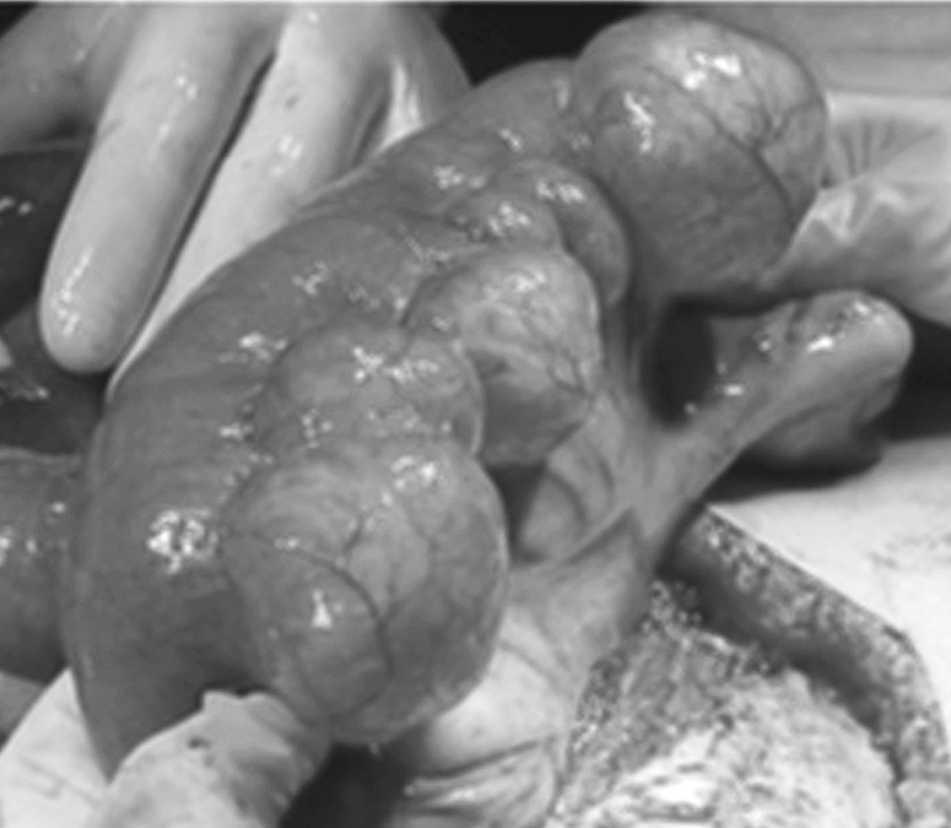

Mujer de 79 años que acude a urgencias por dolor abdominal, náuseas y estreñimiento; con el diagnóstico de suboclusión intestinal se interviene de urgencias, y se evidencia tumoración apendicular y diverticulosis yeyunal masiva (figs. 1 y 2); se le realiza apendicectomía. La diverticulosis se trata de manera conservadora. La paciente evoluciona favorablemente, y se le da de alta sin incidencias. La diverticulosis yeyunoileal es un hallazgo infrecuente, que predomina en edades avanzadas y se estima como adquirida. Tiene una incidencia del 1-5%. Suele cursar de forma asintomática, y es frecuente su diagnóstico en el curso de una laparotomía. Cuando se complica, puede tener su inicio como un síndrome de hipoabsorción con la fisiopatología de un asa ciega cuando son numerosas; hemorragia masiva; obstrucción por adherencias tras inflamación aguda, y retención de un cuerpo extraño con riesgo de perforación. Estas complicaciones suelen ocurrir en el 6-10% de los pacientes. La diverticulosis yeyunoileal asintomática hay que manejarla de manera conservadora, se plantea el tratamiento quirúrgico en caso de complicación; la resección intestinal del segmento afecto con anastomosis primaria es el tratamiento de elección.

Fig. 1.

Fig. 2.

Diagnóstico: Diverticulosis yeyunal.